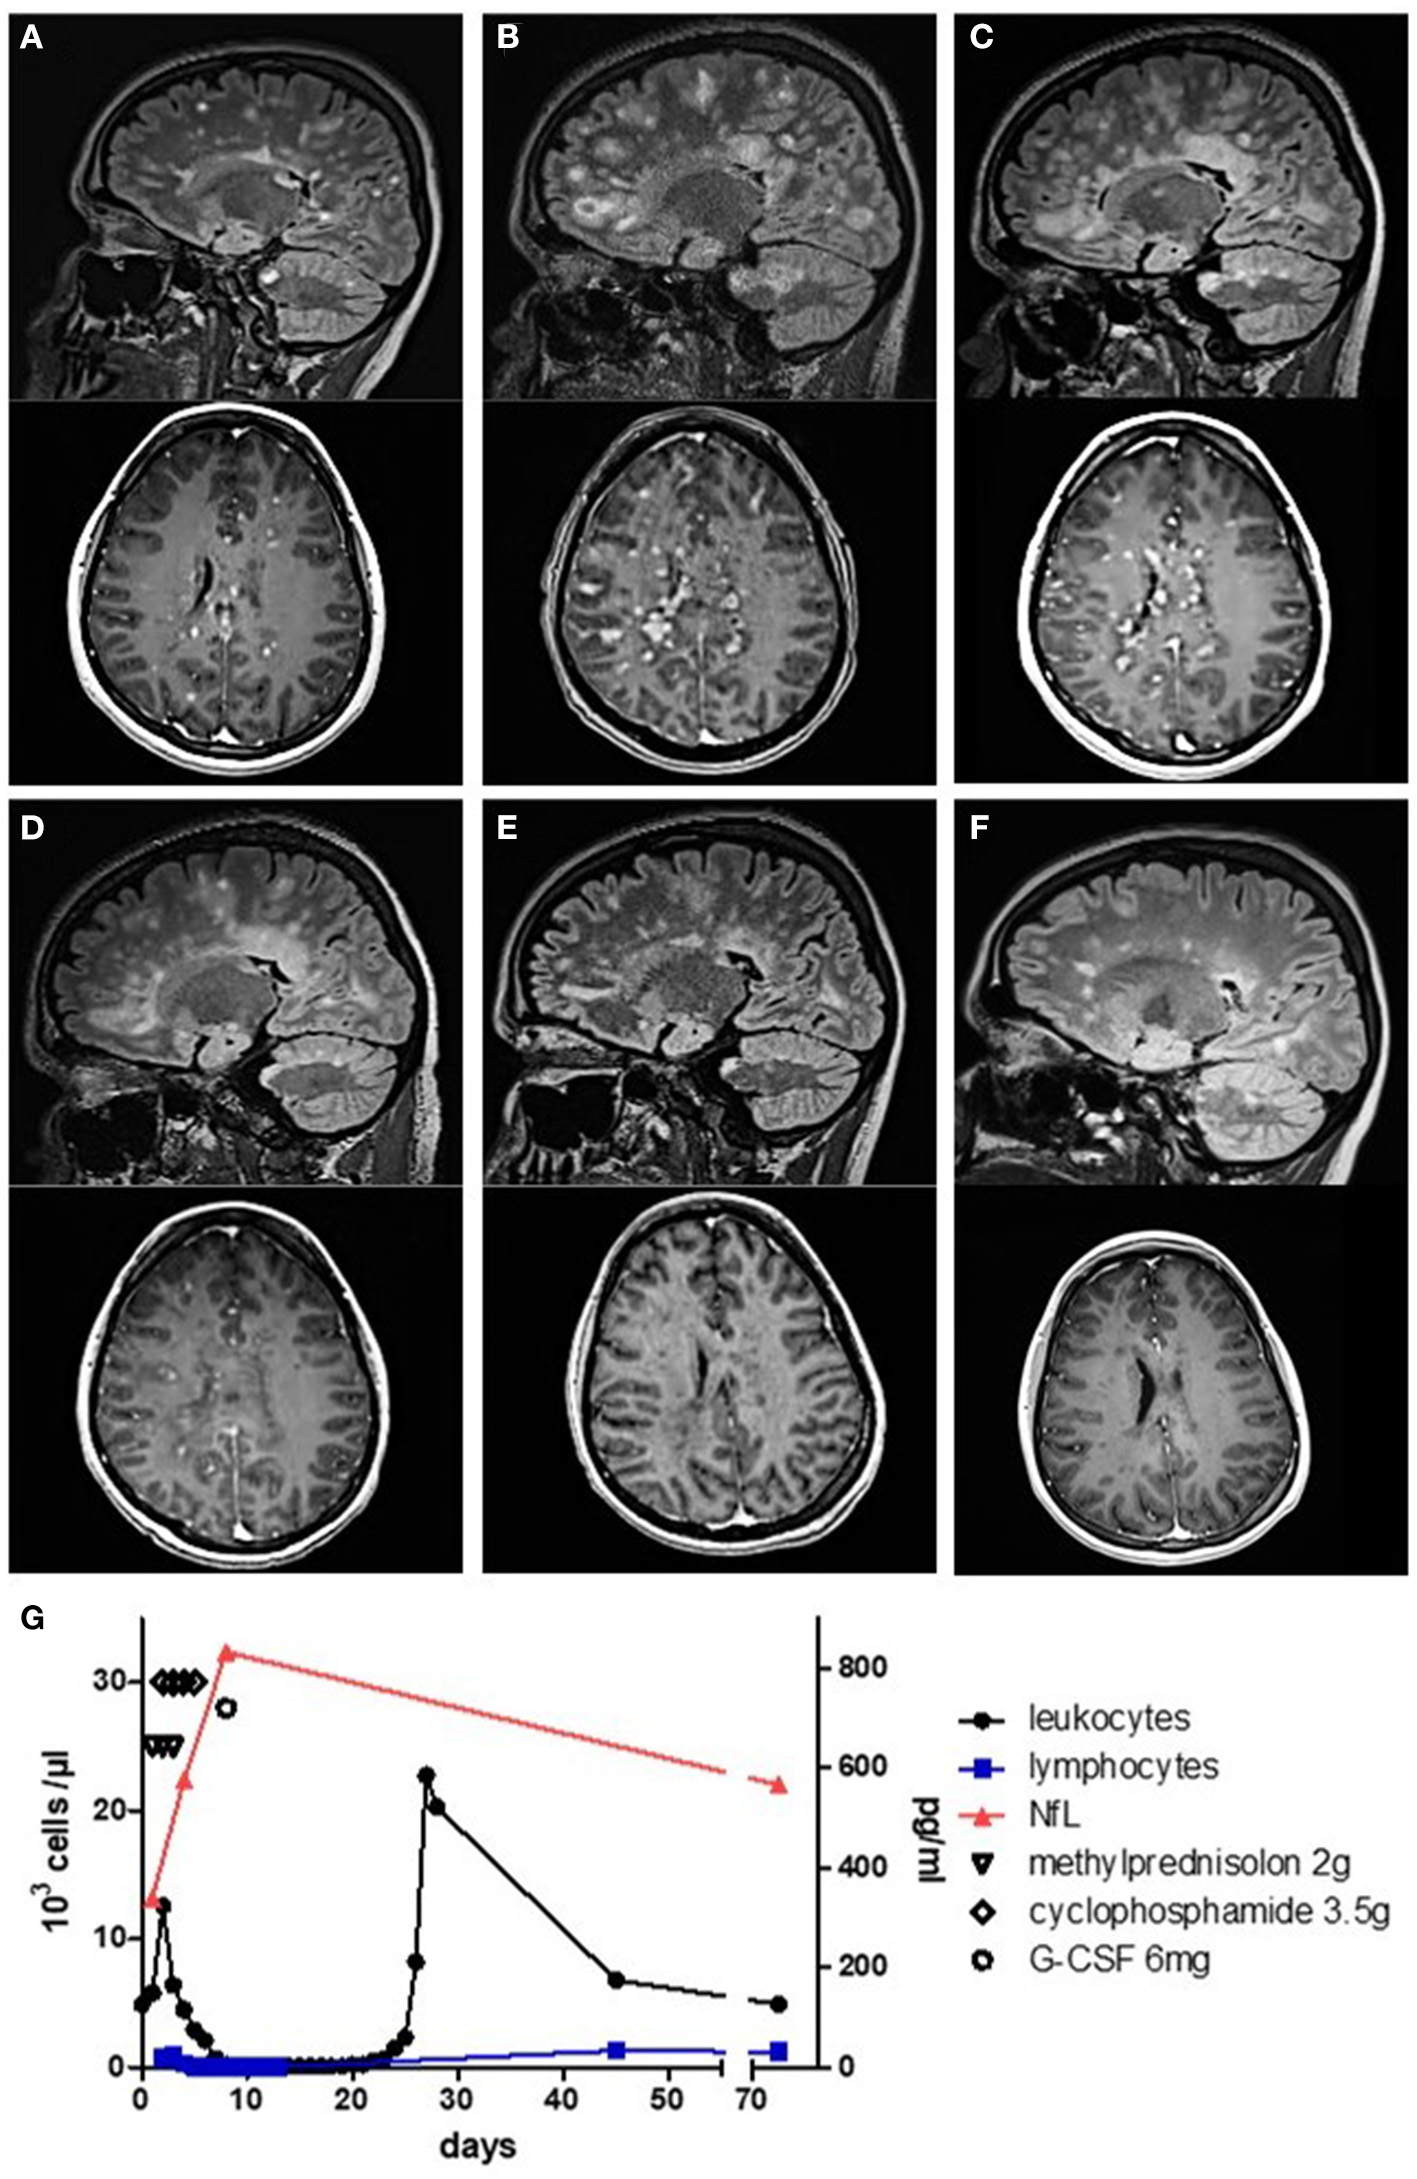

A 26-year-old female patient without a history of neurological symptoms presented to our hospital with bilateral optic neuritis which had gradually developed within 5 days prior to admission. Other than hypothyreosis, her past medical history was unremarkable. The patient complained of mainly left-sided bilateral blurred vision, reduced color discrimination, and pain with eye movement. Visual acuity was impaired on both eyes (left: 20/80; right: 20/40). Ophthalmological examination yielded no retinal abnormalities, but optic coherence tomography (OCT) was not possible as the patient was unable to focus appropriately. She was unable to read letters bilaterally during low-contrast visual acuity (LCVA) testing using 2.5% low-contrast Snellen charts. Visual evoked potentials (VEPs) yielded no response for the left eye, while P100 latencies for the right eye were pathologically increased to 139.5 ms. At admission, neurological examination revealed no further abnormalities. Cerebrospinal fluid (CSF) analysis 9 days after the first occurrence of symptoms revealed a lymphomonocytic pleocytosis of 72/μl with positive oligoclonal bands (OCBs) and intrathecal IgM synthesis. The MRZ reaction (MRZR), anti-AQP4, and anti-MOG antibodies as well as vasculitis screening and virological/microbiological analyses were all negative (see Table 1). 1 day later, intravenous corticosteroids (1,000 mg/day for five consecutive days) were initiated, and on the following day, numerous supra- and infratentorial gadolinium (Gad)-enhancing and non-enhancing T2w as well as two Gad-enhancing spinal lesions consistent with the diagnosis of multiple sclerosis (MS) were seen on MRI (Figure 1A). In detail, there was Gad enhancement in both optic nerves, more than 35 dot-shaped Gad-enhancing juxtacortical/periventricular lesions with typical Dawson's finger configuration, and more than 12 active infratentorial lesions. Due to the typical presentation and the above-described paraclinical findings, we dispensed with further imaging such as magnetic resonance spectroscopy or positron emission tomography–computed tomography. As intravenous steroids resulted in no clinical improvement, five cycles of plasmapheresis and two additional cycles of immunoadsorption were performed. Following this treatment, her sight ameliorated subjectively as she regained the ability to recognize outlines, but overall improvement was poor. While LCVA yielded a score of 0 bilaterally, OCT was now possible, showing a normal peripapillary retinal nerve fiber layer thickness in both eyes (right: 102 μm; left: 103 μm). The patient was scheduled for ocrelizumab therapy within the following 2 weeks and discharged. Regarding other therapeutic options, we decided against alemtuzumab due to her known diagnosis of hypothyroidism. Moreover, the patient was opposed to natalizumab treatment due to concerns regarding progressive multifocal leukoencephalopathy even though she had a negative anti-John–Cunningham virus antibody titer. 1 day after discharge, the patient received the 13-valent pneumococcal conjugate vaccine in preparation for the planned ocrelizumab treatment. Within the next 5 days (i.e., ca. 1 month after the initial symptoms), she experienced a second relapse and was re-admitted to our hospital with a newly developed left spastic hemiplegia and progressive loss of vigilance. MRI revealed a fulminant progression of the lesion load and Gad enhancement with now more than 100 Gad-enhancing lesions (Figure 1B). CSF analysis prior to the following therapy showed a shift to a lymphogranulocytic pleocytosis. Serum NfL was 340 pg/ml as measured by ELISA (Figure 1G). After exclusion of an infectious etiology, a course of intravenous high-dosage corticosteroid (2,000 mg/day for 3 consecutive days) was administered. On the second day of corticosteroid therapy, the patient was started on an additional high-dose cyclophosphamide (HiCy) therapy for 4 consecutive days with 50 mg/kg/day, reaching a cumulative absolute dose of 14 g. Shortly after this combined therapy, serum NfL peaked at 833 pg/ml. 3 days after HiCy therapy, stem cells were mobilized with 6 mg granulocyte-colony stimulating factor. As expected, blood analysis revealed leukopenia and lymphopenia immediately after HiCy treatment. A recovery of the leukocytic population was observed at 10 days later. Circa 3 days after the last dose of cyclophosphamide, we observed both clinical and radiological improvement. While the total lesion load was stable, only 16 lesions were still active (Figure 1C). Peripheral CD34-positive hematopoietic stem cells (HSC) were harvested by leukapheresis 3 weeks later and cryopreserved for future transplantation, if needed. The patient was discharged with mild residual neurological deficits and was closely monitored both clinically and radiologically (Figures 1D–F). Serum NfL levels slowly decreased over the course of 10 weeks to 566 pg/ml. 9 weeks after the HiCy treatment, maintenance therapy with ocrelizumab was initiated following standard dosing (i.e., loading with 300 mg i.v. twice within 2 weeks and 600 mg i.v. as maintenance). 6 months later, the patient was still clinically stable without any relapses. The only residual symptom was a slightly impaired visual acuity (left: 20/30; right: 20/30). The VEP P100 latencies had returned to normal (right, 110 ms; left, 109 ms).

Figure 1

MRI and serological monitoring of the disease course. (A–F) Sagittal FLAIR and axial T1 gadolinium (Gad) sequences. (A) Numerous lesions with Gad enhancement at first admission. (B) MRI at re-admission showing more than 100 Gad-enhancing lesions. (C) Decrease of lesion load 7 days after the first dose of cyclophosphamide. (D) Further decrease of lesion load mirroring clinical remission at 15 days and (E) at 30 days. (F) At 44 days after cyclophosphamide treatment, no more Gad enhancement was detectable. (G) Leukocyte and lymphocyte count as well as serological neurofilament light chain levels during treatment.